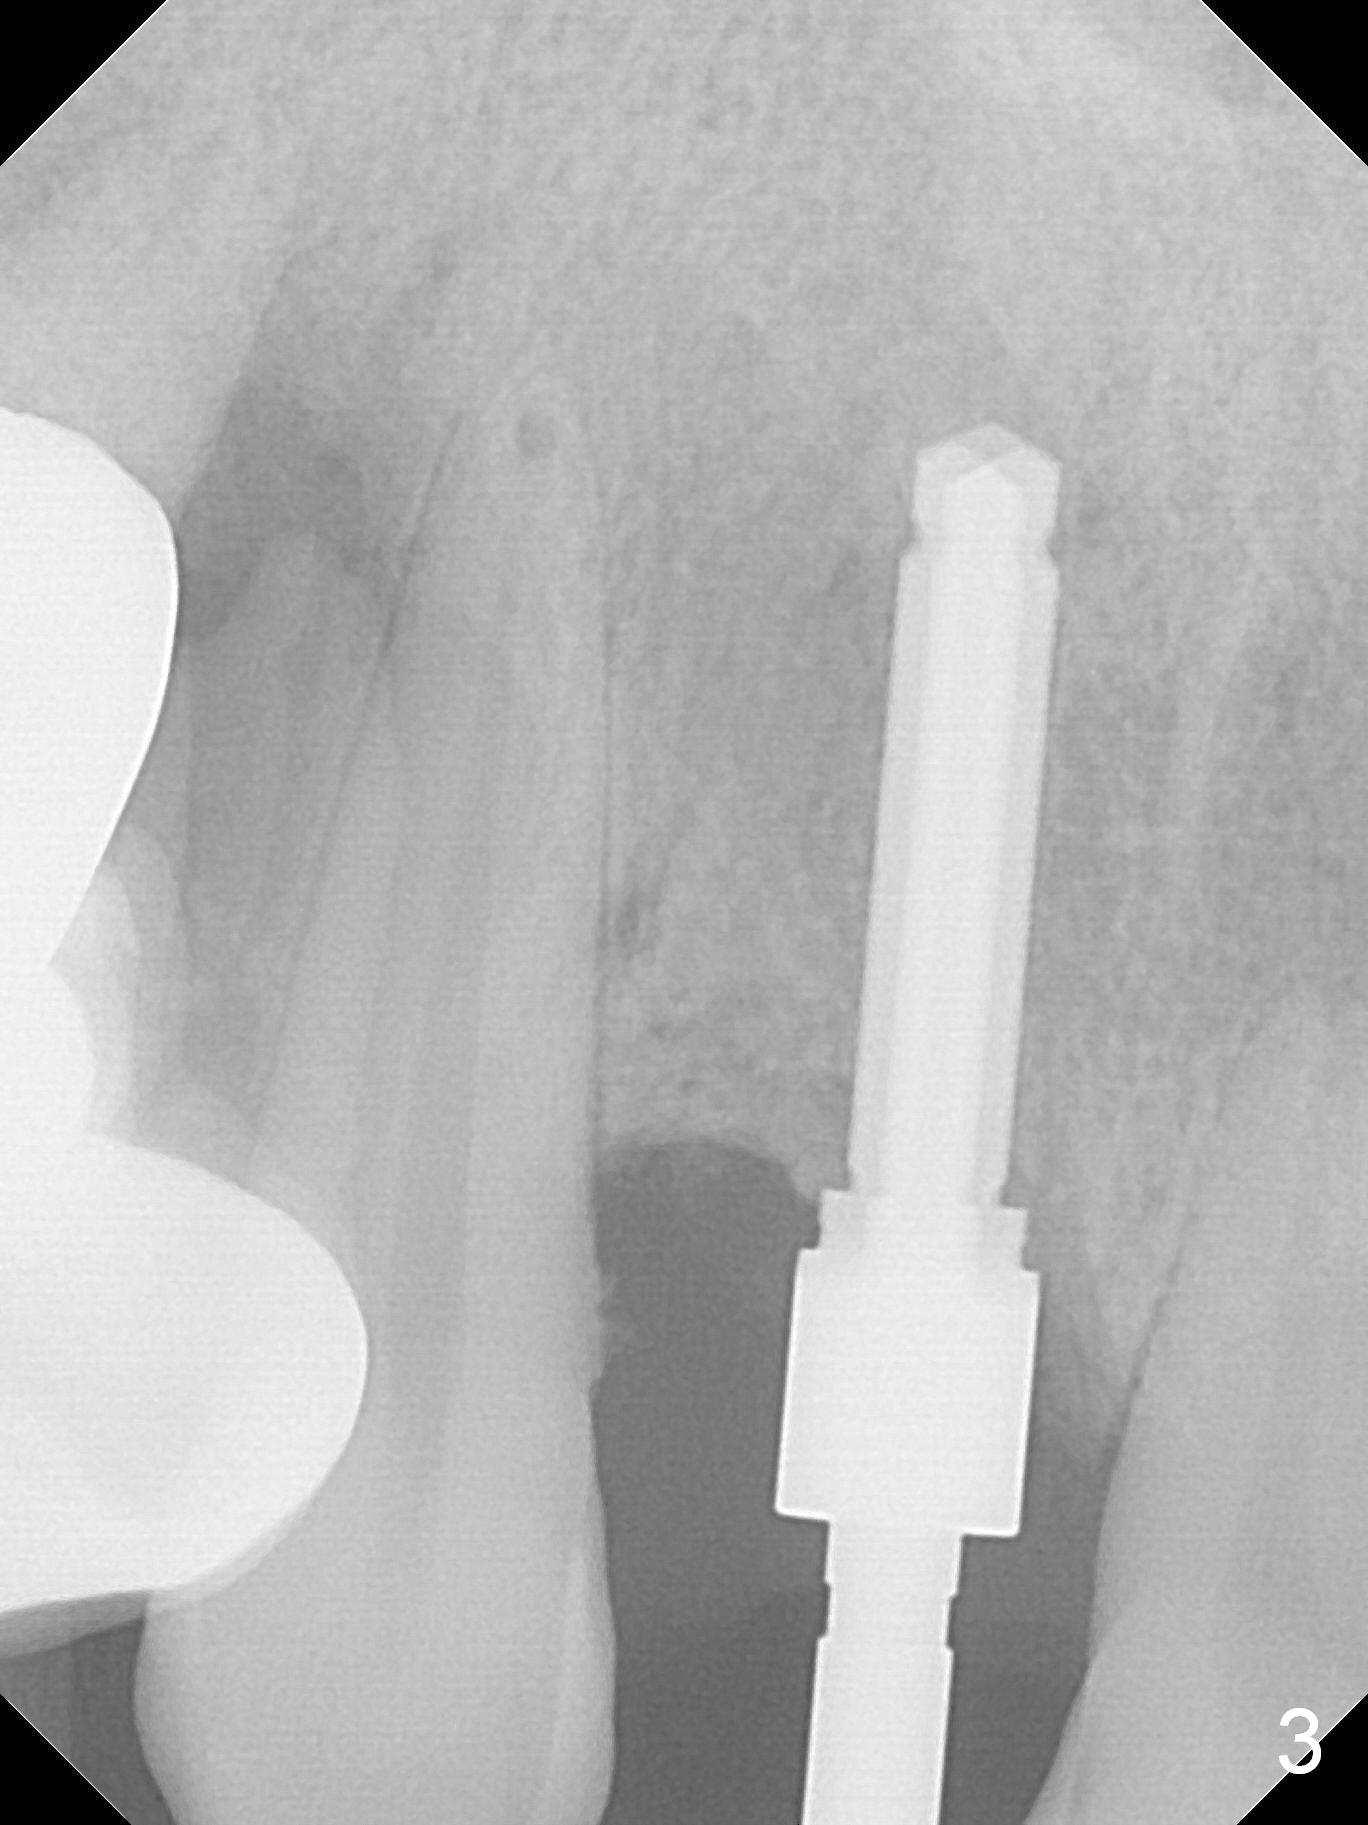

In fact the buccal plate feels to be perforated when 2 mm initial drill is being used probably at the deepest area of the concavity shown in Fig.2 (near B). The trajectory is adjusted and the osteotomy is enlarged by 3 mm drill for 13 mm (Fig.3). When a 3.8x13 mm implant is placed (50 Ncm), an angled abutment is used (Fig.4, 4.5x15°(A)5 mm). As planned, a 3.8x13 mm implant is placed at #13, while bone graft is placed mesial and palatal to #15 implant. No provisional is fabricated from #9 to 15 due to time limitation and lack of parallism between the abutments.